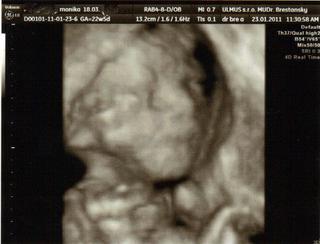

dnes sme boli na tom 4D... no naša malá potvora sa nám ukázala iba na malinkú chvíľočku a potom ani za nič 😀

tak o 2 týždne ideme zasa ale už ju nebude merať už iba kvôli videu aby sme mali peknučké lebo teraz nie je skoro nič v 4 D , lebo to nebolo riadne vidieť.. Keď to mmm donahráva na youtube hodím vám sem link.. malo by to ešte takých 20 minút trvať.

Malinká je krásna a váži cca 572 g 😀 Zodpovedáme 23 tt a 2 d.. sme 22 tt a 5 d... takže je to ok 🙂

STále mala ručičku pred tváričkou 😀

@alena24 - vidím, že váš je ako naša .-D tiež tie ruky pred tvárou. ale aspoň zo začiatku na chvíľu ukázala.. 😀